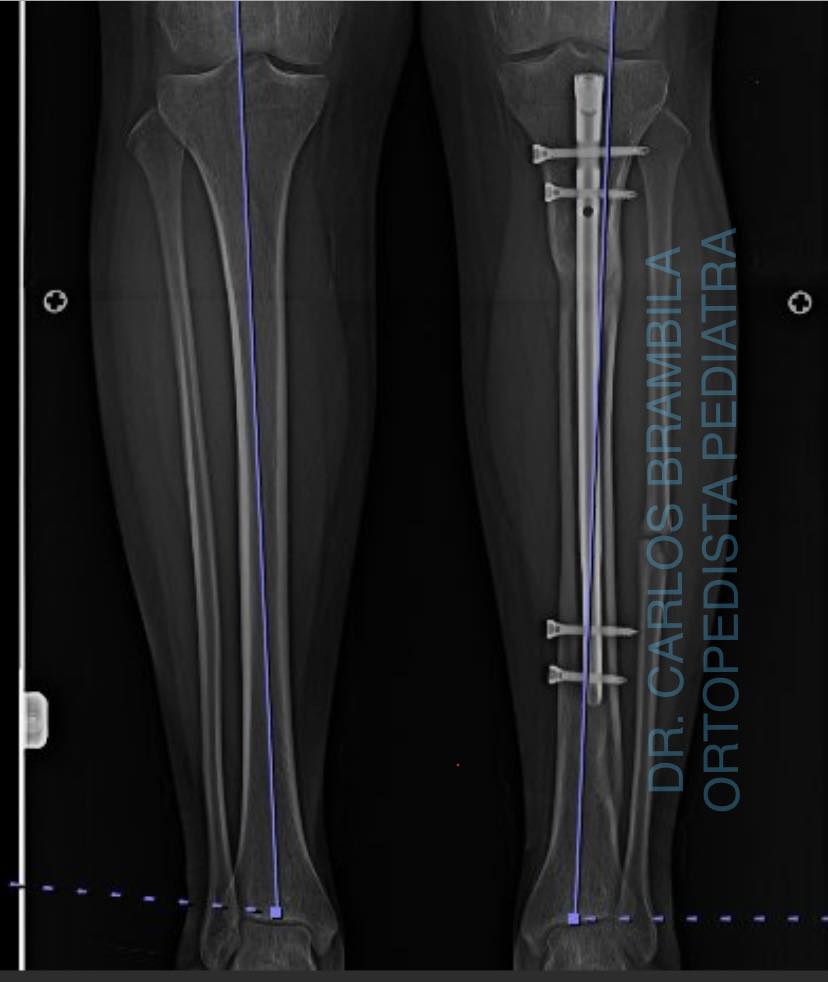

Me complace compartir con ustedes el caso de Karen, una joven de 17 años que acudió a mi consulta por un acortamiento en su extremidad inferior izquierda debido a una fractura de tibia. Después de una evaluación clínica y radiográfica, le realicé una cirugía de alargamiento óseo guiado con clavo centro medular y fijador externo Rekrea. El procedimiento fue un éxito, y Karen recuperó el balance de sus extremidades, eliminando el dolor en su cadera derecha. Ahora, Karen puede realizar todas sus actividades físicas sin problemas y se va feliz y satisfecha. Me siento orgulloso de haber podido ayudarla a recuperar su calidad de vida.